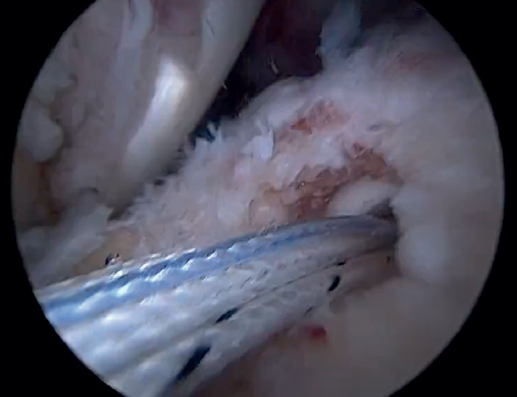

Finally, the anterolateral supraspinatus threads are used in combination with the posterolateral tapes to establish a more lateral double row with two direct anchorings that allow the threads to be threaded through two loops(Biocomposite SwiveLock® C 4.75 × 19.1 mm, Arthrex, Naples, FL, USA). This achieves a tension-free double row repair of the supraspinatus, covering the superior capsular repair made with the LPB (Figure 11).

Once suturing is complete, the arthroscope can be reinserted into the glenohumeral joint to check the final result of the superior capsular reconstruction with the LPB and, especially, the correct repair of the supraspinatus to its footprint on the greater tuberosity (Figure 12).